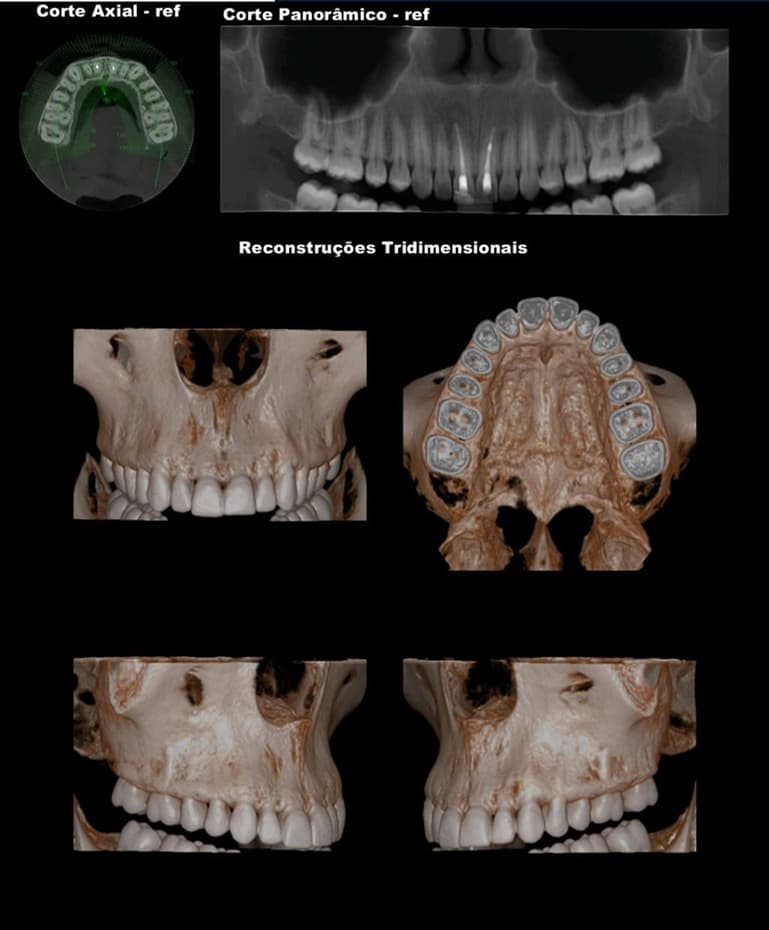

TOMOGRAFIA COMPUTADORIZADA DE ALTA RESOLUÇÃO por feixe Cone Bean - MORITA X800

• MAXILA TOTAL

• MANDÍBULA TOTAL